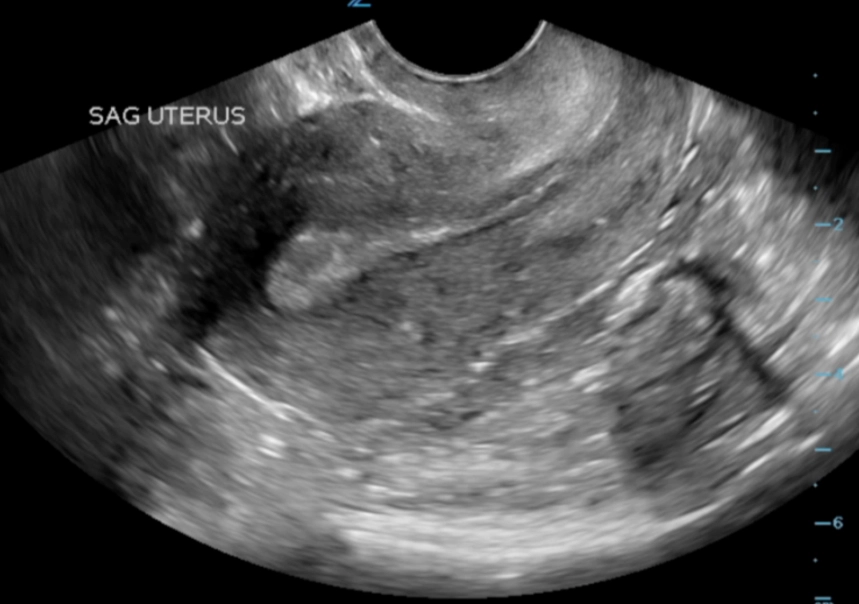

This is closer to the "touch" method, but performed by a trained professional. Around 6-8 weeks, a doctor or midwife may be able to detect subtle signs during a bimanual exam (using fingers inside the vagina and the other hand on the abdomen). They might feel that the uterus is slightly enlarged, softer (Hegar's sign), or the cervix has changed texture. This is a clinical skill developed over years—it's not something you can replicate on yourself.

- Dating the pregnancy accurately via ultrasound.